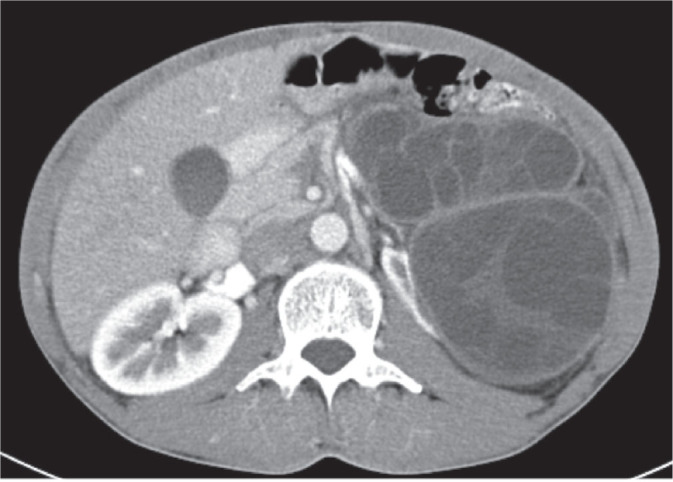

This case report presents a 43-year-old worker (welder in the locksmith trade) from Bosnia and Herzegovina who was diagnosed with advanced hydatidosis during a preventive medical examination. The patient had a history of frequent close contact with dogs at home and at work and reported a long-standing sensation of heaviness in the left side of his abdomen. As part of his routine occupational health examination, he had a complete laboratory testing, abdominal ultrasound, multislice computed tomography (MSCT), and a consultation with an infectious disease specialist and abdominal surgeon. Imaging revealed multiple cystic formations in the left hemiabdomen and a cyst in segment VIII of the liver, confirming the diagnosis of multivisceral echinococcosis. The patient was promptly treated with preoperative (and postoperative) albendazole to reduce the cyst size and prevent complications. This case highlights the critical role of ultrasound in the diagnosis of hydatidosis, especially in an occupational medicine context. As part of preventive screening, ultrasound is a valuable tool for the early detection of echinococcosis in workers in high-risk environments. Early diagnosis allows for timely intervention, reducing the risk of disease progression to an advanced stage. This case underscores the importance of implementing effective epidemiological strategies, including regular screenings and awareness campaigns, in order to control the spread of echinococcosis in endemic regions.

本病例报告涉及一名来自波斯尼亚和黑塞哥维那的43岁工人(锁匠行业的焊工),他在预防性医学检查中被诊断患有晚期包虫病。患者有在家和工作中经常与狗密切接触的病史,并报告其左腹部长期有沉重感。作为常规职业健康检查的一部分,他做了完整的实验室检查、腹部超声、多层计算机断层扫描(MSCT),并咨询了传染病专家和腹部外科医生。影像学显示左半腹多发囊性形成,肝脏第八节段一囊肿,确认多脏器包虫病的诊断。患者术前(术后)及时使用阿苯达唑治疗,以减小囊肿大小并预防并发症。本病例强调超声在包虫病诊断中的关键作用,特别是在职业医学背景下。作为预防性筛查的一部分,超声是在高危环境中早期发现棘球蚴病的宝贵工具。早期诊断可以及时干预,减少疾病进展到晚期的风险。这一病例强调了实施有效的流行病学战略的重要性,包括定期筛查和提高认识运动,以控制棘球蚴病在流行地区的传播。